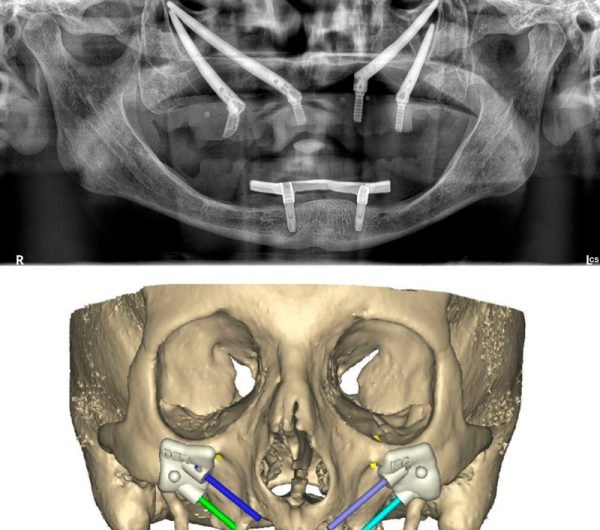

Decidí recuperar mi sonrisa y fui a la clínica dental donde me atendió la Dra. Laura Zárate. Me explico paso a paso como sería el procedimiento. Resolvió todas mis dudas y me dio la confianza para iniciar el tratamiento.